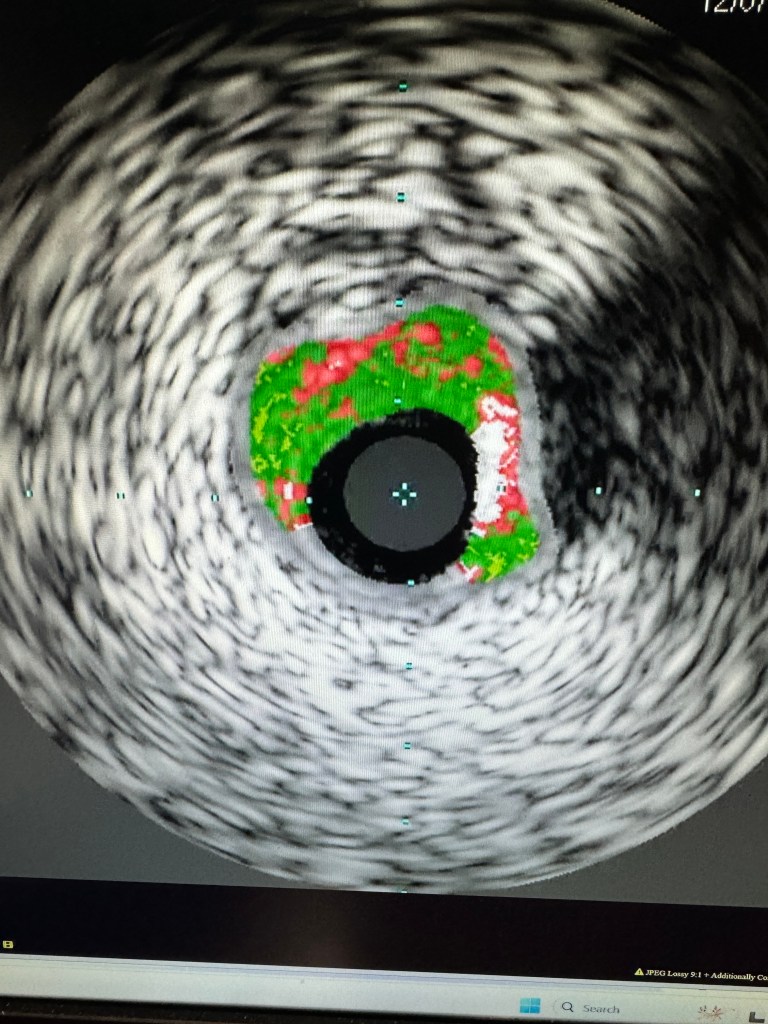

A 75 year old Caucasian female with HTN and Type II Diabetes Mellitus was admitted with few hours of chest pain. EG showed ST elevation in V1V2V3. STEMI team was called. She had no previous history of CAD. Had a negative EKG stress test just 6 months ago.

It took thrombus aspiration with Export catheter, IVUS, and placement of 3 stents totaling 80 mm to achieve this result

EKG stress test is not a reliable predictor of adverse coronary events. it can miss even severe coronary occlusive disease, as demonstrated above; Coronary Calcium score may have increased the sensitivity. The right coronary artery will be tackled two days after the myocardial infarction.